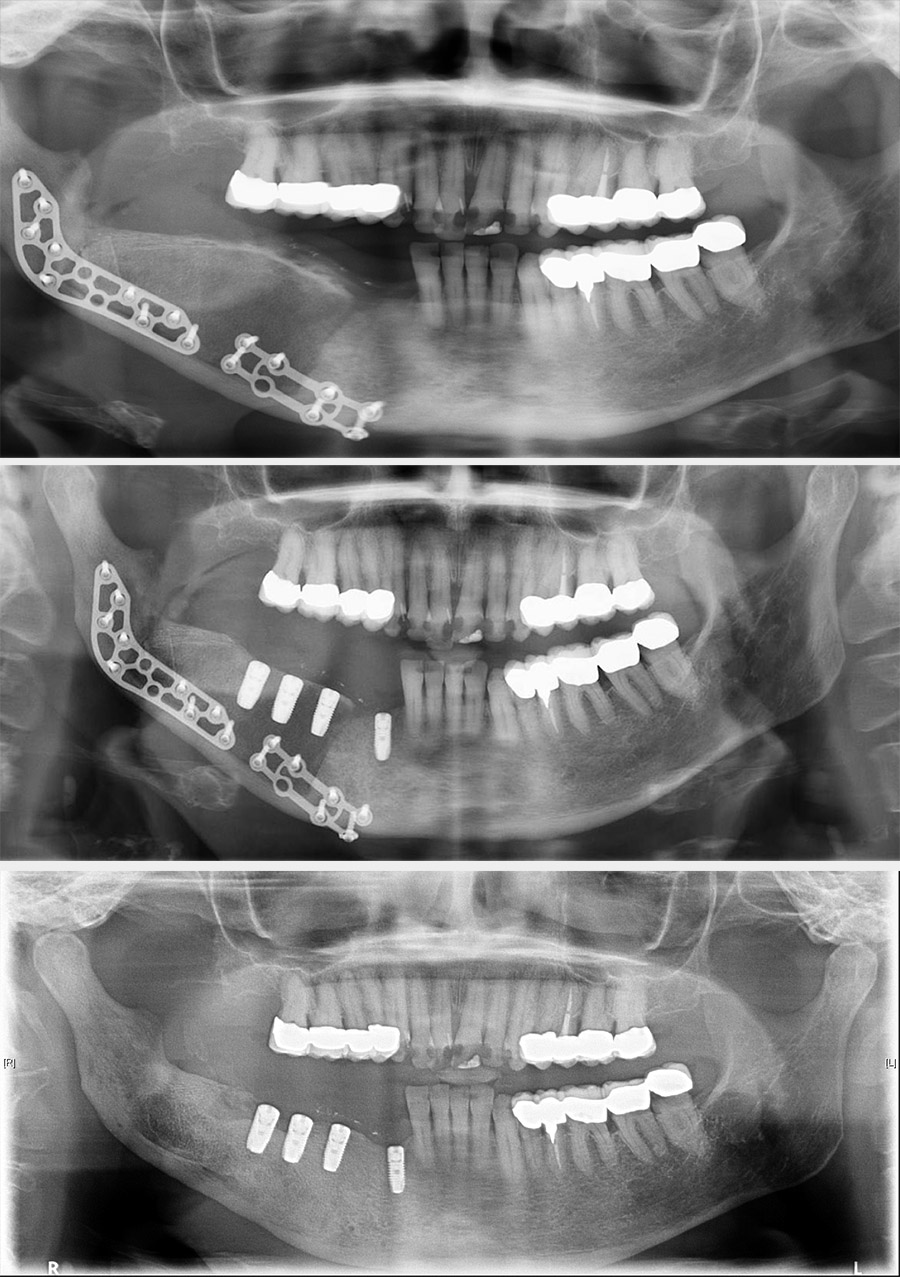

Treatment can be problematic. Long-term antibacterial therapy has been reported as being of benefit if given early in the course of the disease, but there are also reports that high-dose long-term antibacterial therapy has no beneficial effects. In more refractory cases, a course of corticosteroids and decortication may be of benefit. Hyperbaric oxygen therapy can be used to supplement the surgery although the evidence base is conflicting. Bisphosphonates have been advocated for chronic pain but have obvious conflicting risks regarding development of osteonecrosis. In some cases, more radical surgical intervention is required, such as resection of the affected region of the mandible (Figure 1 and Figure 2; note that the surgical techniques are essentially the same for some benign and malignant (see below) conditions).

Figure 2: Postoperative condition. Top: X-ray image 6 weeks postoperatively; middle: X-ray image 4 months postoperatively, bone graft shaped and implants placed for dental rehabilitation; bottom: X-ray image 18 months postoperatively, reconstruction plates removed, implants integrated and ready to be loaded.